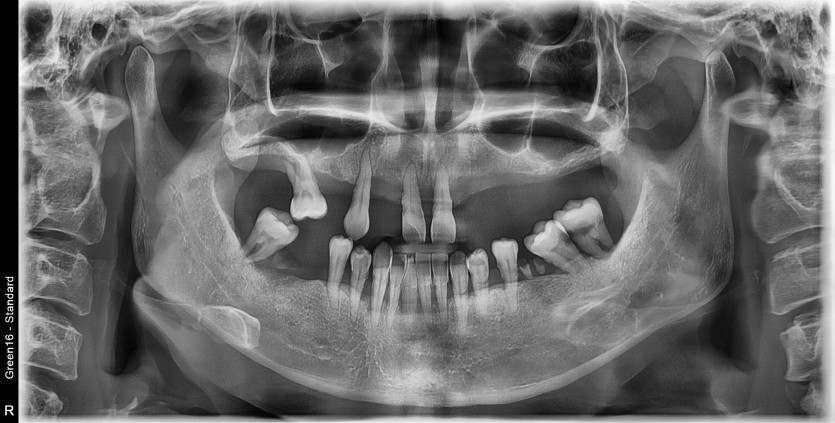

전체 임플란트 증례입니다.

18개의 임플란트로 완성하였습니다.